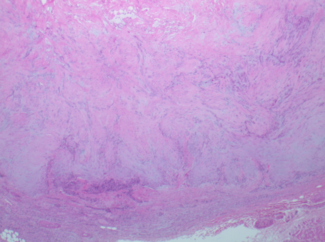

Angioleiomyomas are uncommon, difficult to diagnose clinically, and rarely diagnosed until after excision and histopathological examination. In this case study, the authors report an unusual occurrence of an angioleiomyoma at the region of...